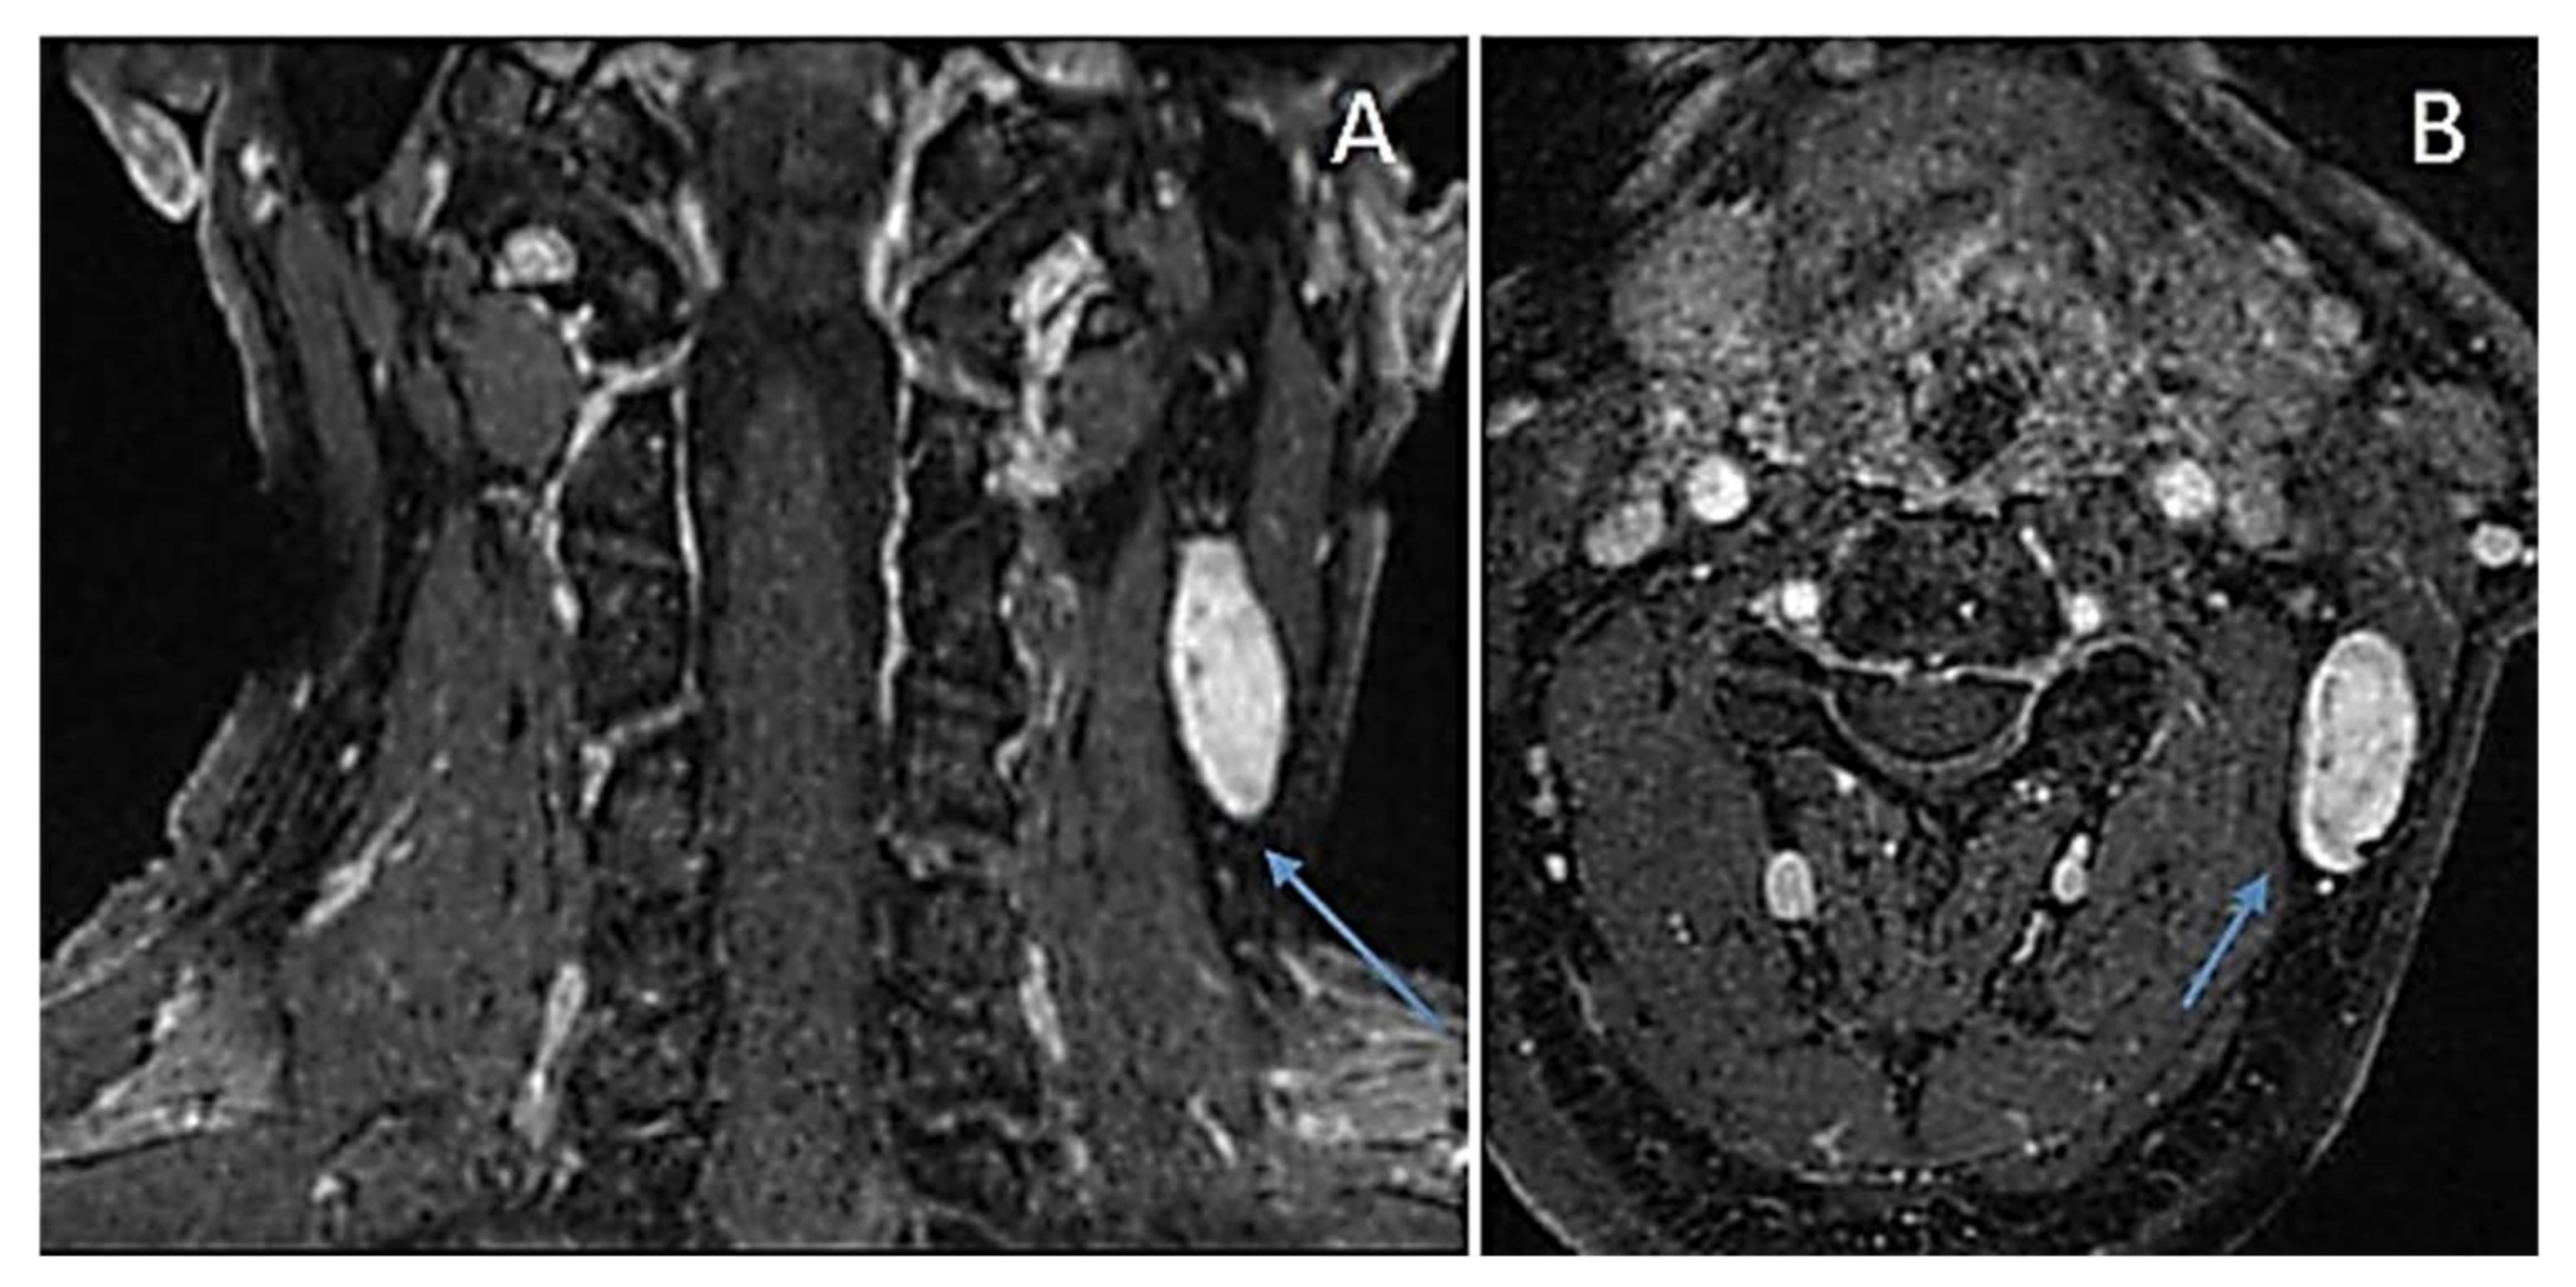

Definition |

|

Clinical Features |

Gross Pathology |

Histopathology |

Immunohistochemistry |

Molecular Diagnostic Features |

Treatment/Prognosis |